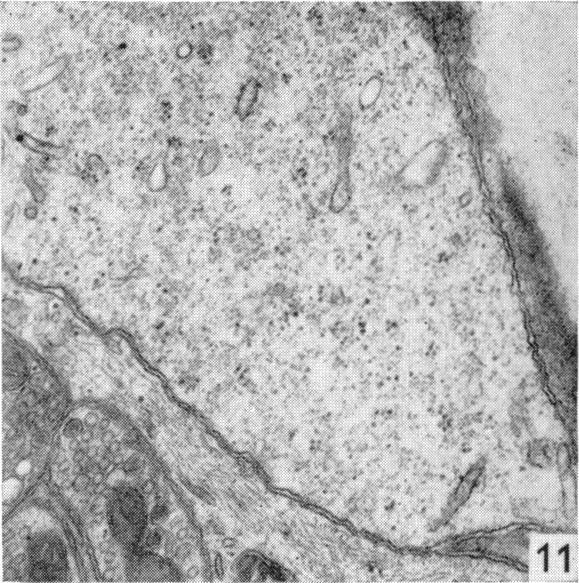

Fine structure of the myenteric plexus in the guinea-pig ileum.

J Anat. 1972 Jan;111(Pt 1):69-97.